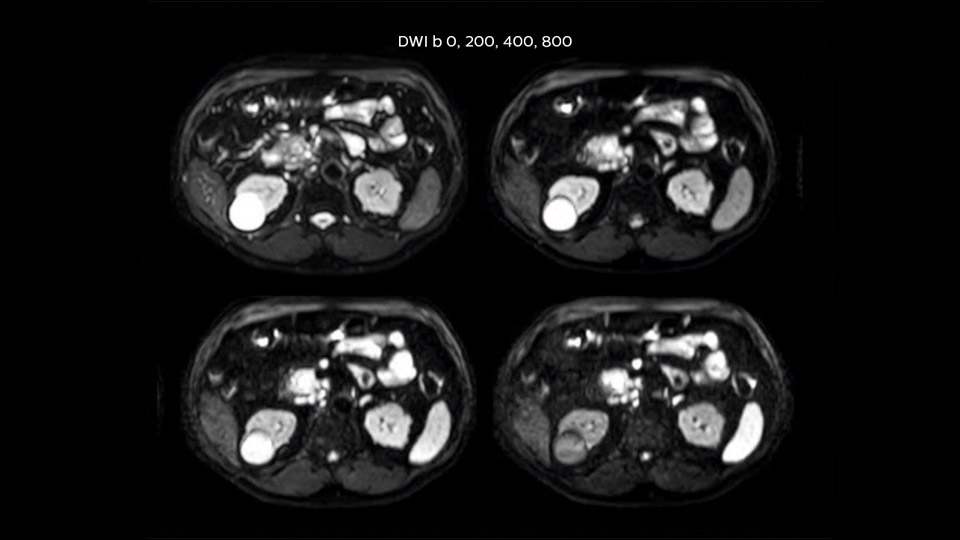

“We acquire one transversal high resolution T2-weighted sequence with 3 mm slice thickness, for example for pancreas or liver lesions. Then we also add a T2 fat suppressed MultiVane XD SPIR sequence. We perform these two routinely in our liver imaging. We use high dS SENSE factors to significantly shorten scan times to 2-4 minutes, which can improve our protocol; it’s a very robust scan.”